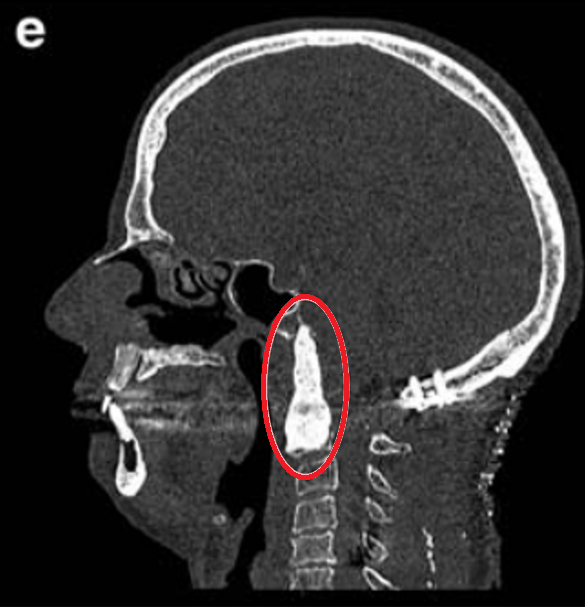

▼E完全切除肿瘤术后用骨水泥填充术腔,从中斜坡到C2椎体水平。术后10天进行枕-颈固定术。

▼F手术顺利,术后MRI显示肿瘤完全除,患者在第一次手术后10天接受了枕颈固定,没有任何并发症。

术后进行质子治疗,术后9个月未观察到影像复发的证据,此外,临床检查显示没有神经系统缺陷,患者恢复正常的日常活动。